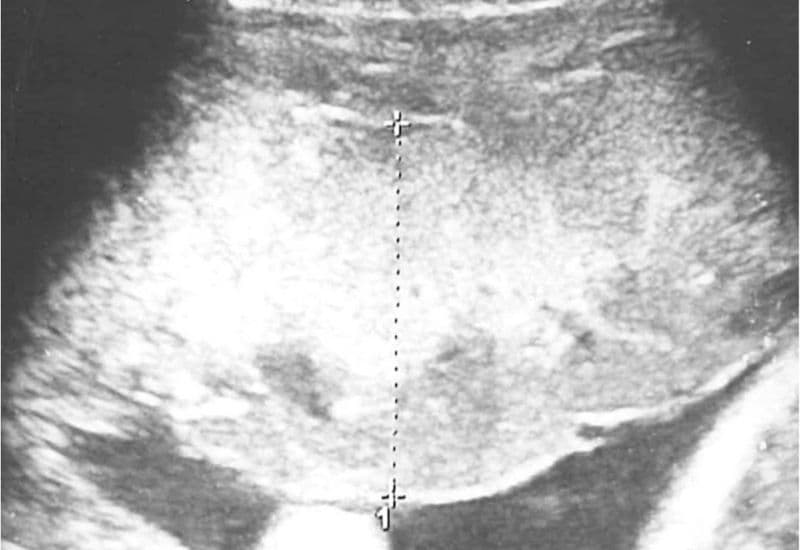

Thông thường, bề dày bánh nhau vượt quá 4cm sẽ được các bác sĩ chẩn đoán là bánh nhau dày hoặc phù bánh nhau. Rất nhiều thai phụ khi nhận được kết quả này đã hoang mang không biết bánh nhau thai dày có nguy hiểm không. Theo các tài liệu y khoa, đây là một tình trạng bệnh lý làm nhau thai ứ nước, tăng thể tích và dần mất đi chức năng dinh dưỡng cho bào thai.

Theo PubMed, việc thực hiện siêu âm liên tục và làm các xét nghiệm kiểm tra sức khỏe thai nhi hàng tuần (đặc biệt trong tam cá nguyệt thứ ba) là bắt buộc.